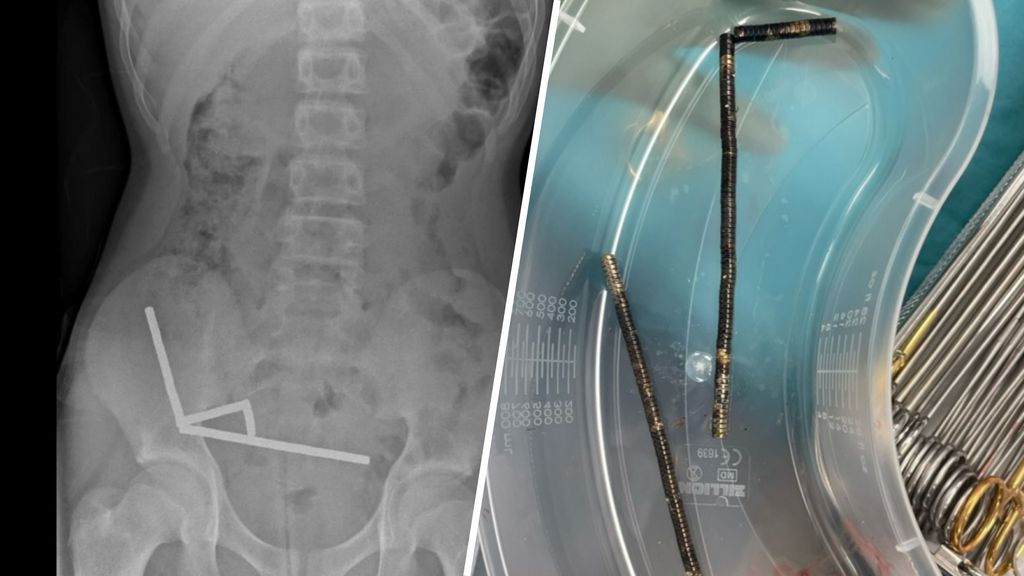

Een tiener uit Nieuw-Zeeland heeft een zware operatie ondergaan, nadat hij tachtig tot honderd kleine, sterke magneten had ingeslikt. Artsen moesten delen van zijn darmen verwijderen, omdat deze afstierven: de magneten trokken naar elkaar toe, waardoor de darmwand beschadigde.